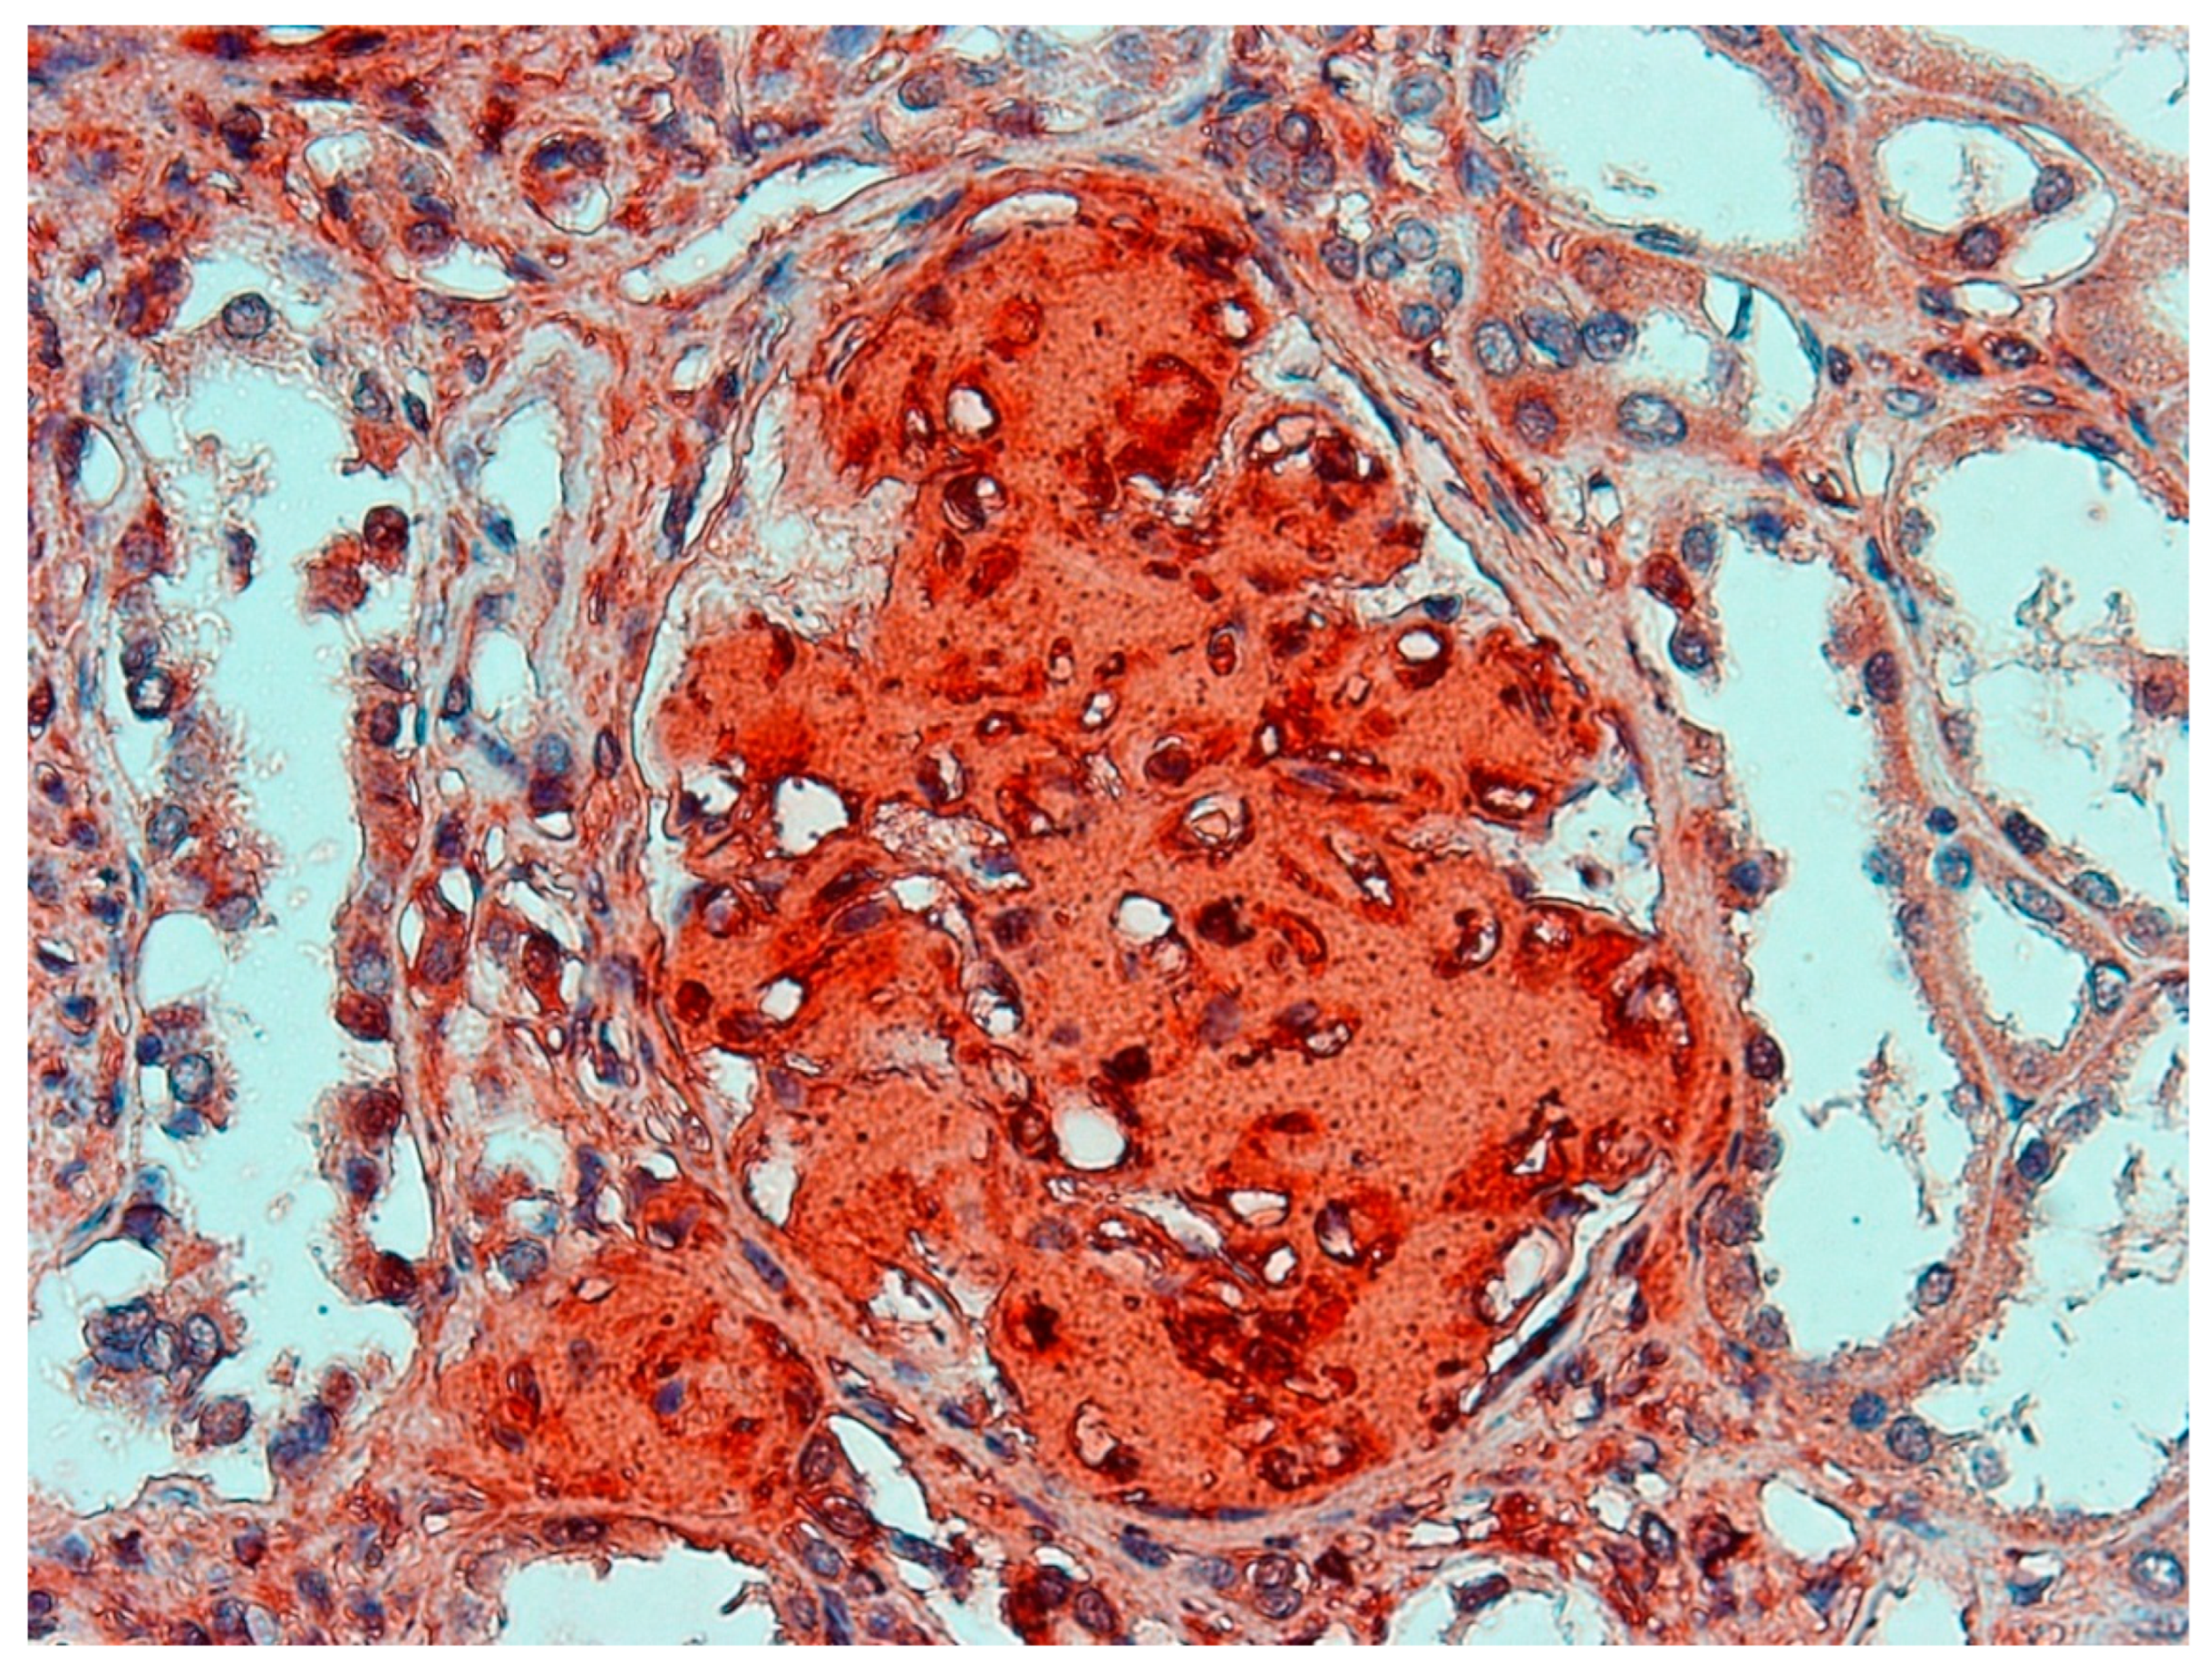

2. Case Report

3. Autopsy